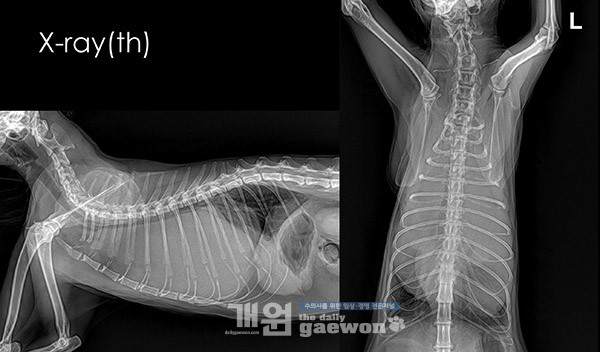

기침과 쥐어짜는 듯한 호흡을 하며 이틀 전부터 식욕저하 증상을 보여 방사선, 혈액검사, 초음파 등을 진행하였습니다. 혈액검사상 큰 이상이 없었는데, 방사선상[그림2] 흉수로 의심되는 양상을 보여 폐초음파를 하였고[그림3], 초음파 상에서 fluid가 많이 보여서 CT검사와 흉수 검사를 진행하였습니다.